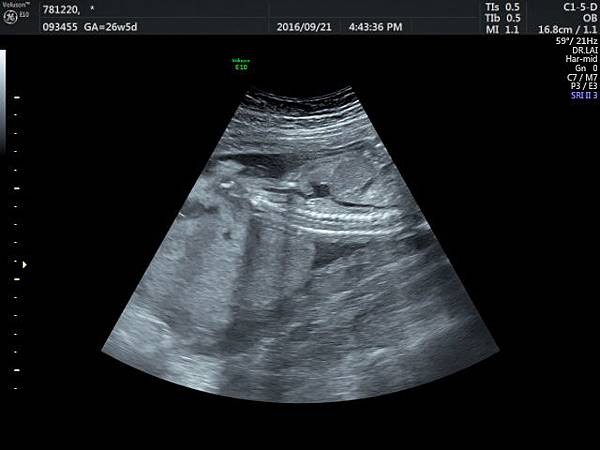

2016. 9. 21.

賴錫鉅

2016年9月21日幫一位懷孕26歲懷雙胞胎的孕婦看胎兒心臟超音波,孕婦目前26週,雙胞胎大小相差四週,高層次超音波除了小的胎兒臍動脈血流有問題之外,沒有其他異常發現,經過我的檢查,我的診斷是小的胎兒有持續性左側上腔靜脈(附圖1~5)。

正常情況左側的上腔靜脈在胚胎發育過程應該要退化,左側頭頸部的靜脈回流是流向右側的上腔靜脈再回到右心房,而持續性左側上腔靜脈是這條血管沒有退化繼續存在,它的血流一般會流入左心房背部的冠狀竇(coronary sinus)再經由冠狀竇回到右心房,因為最終都是回到右心房,理論上沒有什麼問題,只是為何它會不退化呢?是否有什麼因素造成它不退化這才是重點所在,所以做染色體基因檢查的理由就是找出是否有原因。